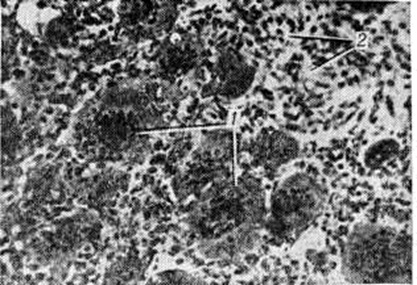

Рис. 2.

Рентгенограммы костей предплечья (а, б)и голени (в) при остеобластокластоме: а — прямая рентгенограмма проксимального отдела предплечья при ячеистом варианте остеобластокластомы; эпиметафиз лучевой кости резко вздут, с истончённым корковым слоем и ячеистой перестройкой губчатого вещества; б — прямая рентгенограмма дистального отдела предплечья при остеолитическом варианте остеобластокластомы; эпиметафиз лучевой кости резко вздут, корковый слой истончён или полностью отсутствует, ячеистая структура костного вещества не определяется; в — прямая рентгенограмма коленного сустава и проксимального отдела костей голени при краевом расположении остеобластокластомы; эксцентрическое вздутие (указано стрелками) эпиметафиза большеберцовой кости, корковый слой истончён, но сохранен на всем протяжении.

При ячеистом (трабекулярном) варианте наиболее характерным является признак вздутия эпиметафиза с истончением, но сохранением коркового вещества (рисунок 2, а). Поражённая кость приобретает булавовидную форму. Одновременно в результате остеобластической функции опухоли наблюдается грубоячеистая перестройка губчатого вещества эпиметафиза — появление крупных и немногочисленных перегородок, а также более нежной и густой сетки. В этом случае отличить Остеобластокластома от аневризматической костной кисты иногда удаётся лишь гистологически. В структуре опухоли, как правило, отсутствуют отложения солей кальция, контуры Вздутого участка кости достаточно гладки в отличие от энхондромы, которая нередко характеризуется наличием крапчатых теней обызвествления и волнистостью контура поражённого участка кости. Зона поражения чётко отграничена от соседних неизменённых отделов кости тонкой склеротической каймой, образующей вместе с истончённым корковым веществом капсулу опухоли. При распространении опухоли в сторону диафиза можно наблюдать на границе опухоли и трубчатого отдела кости так называемый телескопический переход: диафиз как бы вставлен в нависающий над ним вздутый эпиметафиз. Нередко здесь же определяются полоски окостеневающей надкостницы. Хрупкость коркового вещества, покрывающего опухоль, в некоторых случаях может обусловить возникновение патологический надломов с репаративным, нередко бахромчатым периостозом.

Остеолитический вариант строения Остеобластокластома наблюдается или первично, с самого начала роста опухоли, или вторично, в результате перехода из ячеистого варианта. Рентгенологические картина при этом несколько напоминает остеолитическую саркому. Однако в отличие от неё наблюдается истончение и вздутие коркового вещества, покрывающего изменённый участок кости (рисунок 2, б). Ячеистость структуры полностью или частично отсутствует. Вздутое и истончённое корковое вещество может подвергнуться почти полному рассасыванию, но в основании опухоли, в месте её перехода в неизменённую кость, обычно видны остатки раздвинутого и истончённого коркового вещества, что при остеолитической саркоме, как правило, отсутствует. Так называемый телескопический переход диафиза в опухоль при этом рентгенологическое варианте наблюдается ещё чаще, чем при ячеистом.

Рентгенологически различают центрально расположенные и краевые Остеобластокластома Краевые опухоли (рисунок 2, в) обычно не захватывают центральных отделов эпиметафиза. Диагностика их затруднена, но вполне возможна на основе учёта рентгенологическое признаков — вздутия, ячеистости, отсутствия периостального козырька и другие